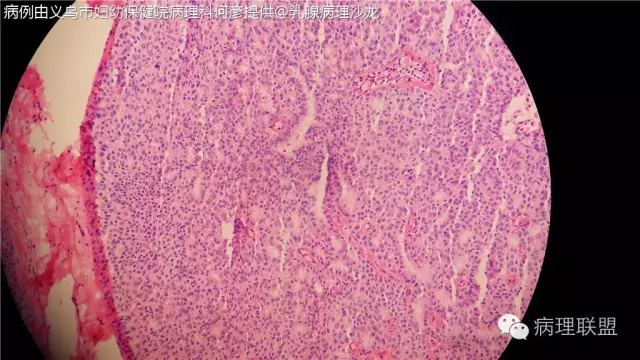

女,56岁,乳腺冰冻病例。(病例由义乌市妇幼保健院病理科何彦提供 ,致谢!)